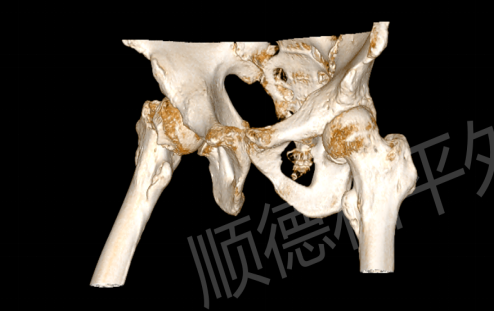

事发当天下午,陈阿姨(化名)在家中不慎摔倒,右侧臀部重重着地,瞬间传来剧烈疼痛,无法站立行走。家人紧急将其送往附近医院检查,X线片提示“右股骨颈骨折(GardenIV型)”,这是股骨颈骨折中较为严重的类型,保守治疗效果差,且极易导致股骨头坏死等后遗症。为寻求更优质的治疗方案,陈阿姨在家人的陪同下转至顺德和平外科医院急诊。

我院急诊医生接诊后,迅速完善相关检查。专科查体显示,陈阿姨右髋关节轻度肿胀,局部压痛及纵向叩击痛明显,髋关节活动严重受限,患肢较健侧短缩2cm,万幸的是远端各趾血运、感觉及活动正常。结合外院影像学资料,“右股骨颈骨折”诊断明确。更棘手的是,陈阿姨年事已高,基础疾病较多,这无疑增加了治疗的复杂性和手术风险。